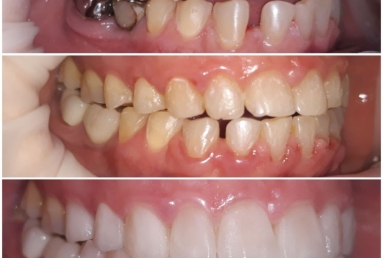

orthodontic treatment, full ceramic crowns

Our patient had general dental abrasion due to maloclusion. After orthodontic treatment, the upper teeth received full ceramic crowns, while the lower were restored with crowns and veneers.

We managed to solve partialy the orthodontic problem and at the same time restore the frontal teeth with esthetic ceramics for a perfect smile.